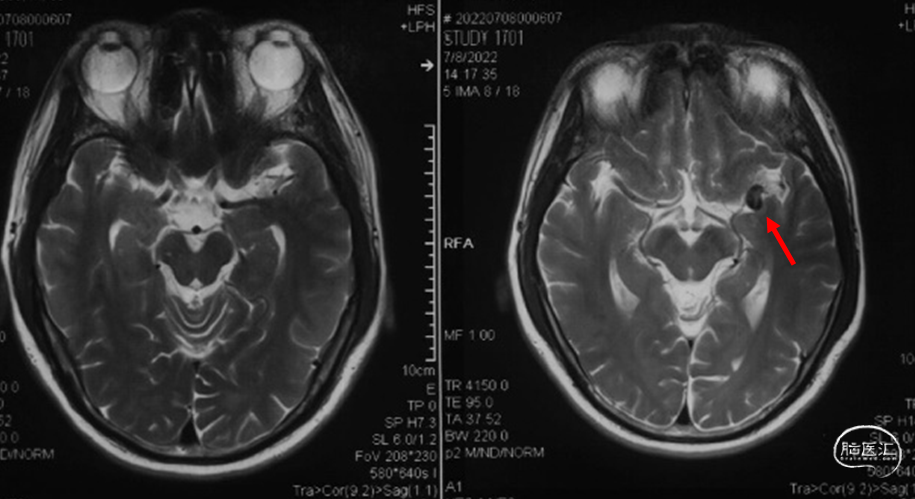

术前头颅核磁:T2象可见血管流空影,增强序列见侧裂区异常血管影。(07-08)